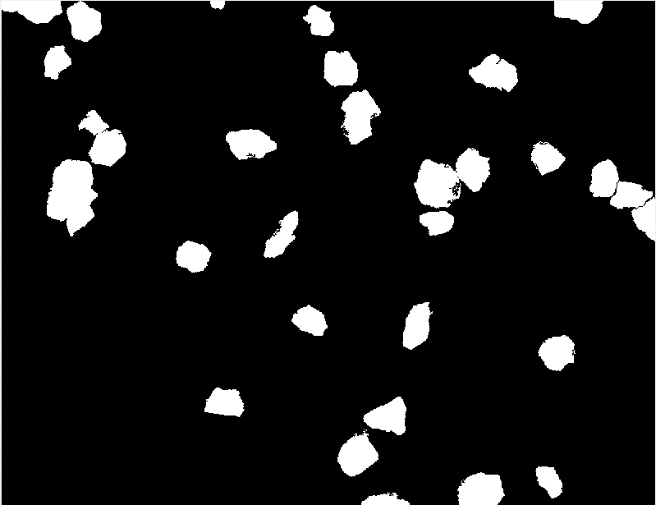

本文结合了宫颈细胞病理学理论基础,以宫颈细胞涂片图像的分割,特征参数提取为目标,使用图像处理等技术,对宫颈细胞图像的分割技术,特征参数的计算和提取进行了系统研究,并完成了相应的系统实现。主要包括:(1)针对Otsu法对宫颈细胞图像分割的精度不够高和效率低等问题,采用基于图像色彩变换,滤波去燥,形态学重构等方法对细胞图像进行预处理,提高分割的准确性;(2)在Otsu法粗分割出细胞质和细胞核的基础上,使用基于局部最小值的改进的分水岭方法进行单细胞的精确分割和重叠细胞质的分割,根据宫颈细胞质和细胞核的定位区分出杂质和细胞;(3)在宫颈细胞图像特征定量分析方面,在处理后的图像上提取了有效的形态学和纹理特征,包括细胞核圆形度、细核面积、核长宽比、胞浆比、粗糙度等。

本文提出的方法,与传统的分水岭算法相比,显著抑制了过分割现象,对于边缘清晰的单细胞和重叠后不太模糊的细胞团,分割效果较理想,显著提高了分割算法的精度。

This article combines the theoretical basis of cervical cytopathology, using cervical smear image segmentation, feature parameter extraction as the goal, and using image processing techniques to systematically study cervical cell image segmentation techniques, feature parameters calculation and extraction. And implement the corresponding system. The main contents are as follows:(1) For the problems of Otsu's method on the accuracy of image segmentation of cervical cells is not high enough and the efficiency is low, such methods as image color transformation, filtering and desiccation, morphological reconstruction are used to preprocess the cell image and improve segmentation accuracy; (2) On the basis of coarse segmentation of cytoplasm and nucleus by Otsu method, an improved single-cell segmentation and overlapping cytoplasm segmentation were performed using an improved watershed method based on local minima, and distinguish impurities and cells based on the location of cervical cytoplasm and nuclei; (3) In the quantitative analysis of image characteristics of cervical cells, effective morphological and texture features were extracted on the processed images, including circularity of nuclei, area of nuclei, ratio of nuclear to aspect ratio, and cytoplasm ratio, roughness, etc.

The proposed method, compared with the traditional watershed algorithm, significantly suppresses the over-segmentation phenomenon. The segmentation effect is ideal for single-cells with clear edges and overlapping cell cluster with clear contour, which significantly improves the accuracy of the segmentation algorithm.

第三章根据宫颈细胞图像中细胞核和质颜色,形态特点,提出了几种分割方法,包括对宫颈细胞图像的粗分割,ROI区域提取,基于Otsu和改进分水岭的重叠宫颈细胞图像的分离方法,并对相关方法进行模拟和实验验证。